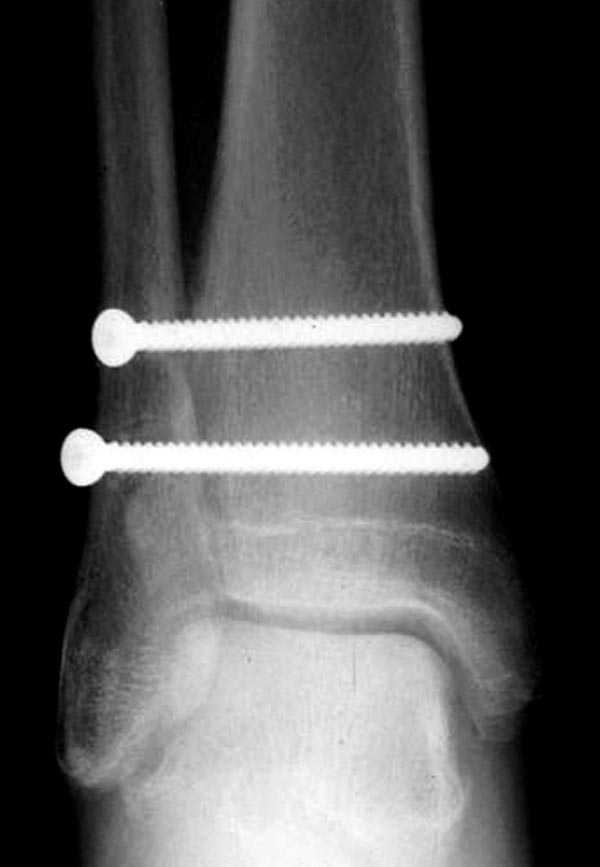

Две параллельных шурупа создают условия для сращения мембраны и синдесмоза, 8 недельный срок достаточен, и можно удалить фиксаторы.

Без оперативного лечения Межкостная мембрана будет источником боли у спортсменов.